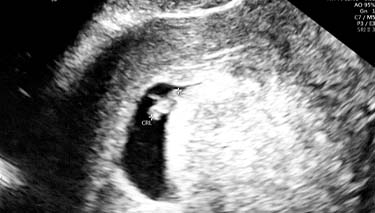

At 6 weeks, it can be difficult to see in much detail how the baby is developing. But the size of the baby and the sac it is growing in will give important information about how your little baby is growing. It may even be possible to see your baby's heartbeat.

At 6 weeks, your baby should measure approximately 5-9mm long or be about the same size as a lentil.

6 weeks into your pregnancy is also the earliest time you might be able to see a foetal heartbeat on the ultrasound monitor. It will be very faint at this stage and depending on the ultrasound equipment being used, you and the sonographer may not be able to see it at all. If a heartbeat can be seen, this can be seen as a tiny, flickering pulse on the screen.

Don t be alarmed if all you see on the ultrasound screen is a small, empty circle. It's still very early days and it's common for only a yolk sac to be visible.